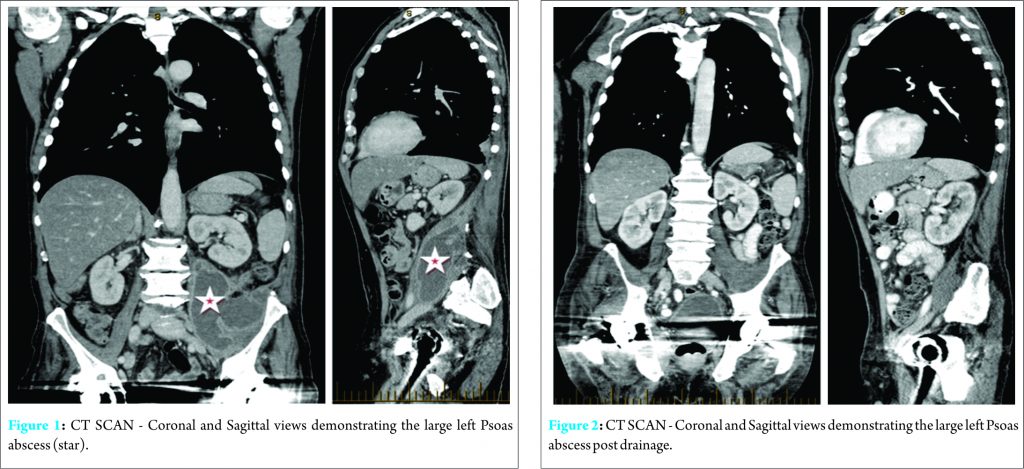

A 68-year-old man presented with sepsis and a two-month history of general malaise and 18kg weight loss. His past medical history includes elective right and left hip replacements, 22 and 14 years ago, respectively. The left hip replacement was complicated with two dislocations, which were both managed with closed reduction and no complications were reported in the right hip. This is on a background of haemachromatosis with no evidence of end organ damage, thoracic shingles with no residual post-herpetic neuralgia, well-controlled gout, osteoarthritis, and a 20-pack /year history of smoking. Physical examination revealed a tender palpable mass in the left lower quadrant. Laboratory findings were as follows: haemoglobin 7.9 g/L; white cell count 8.5 x 109/L; neutrophil 6.29 x 109/L; platelet 625 x 109/L; C-reactive protein 82mg/L. CT of the chest, abdomen and pelvis identified a large left psoas abscess as seen in (Fig. 1). The psoas abscess was surgically drained and more than one litre of pus was produced. A 24 Fr 3-way catheter was inserted for irrigation of the cavity and a Yates drain was inserted in dependent position for ongoing drainage. The cavity was irrigated with normal saline twice daily, and then reduced to once daily four days post-operatively when the runoff remained clear and there was minimal residual drainage. He was empirically treated with IV Tazocin, and then switched to IV Flucloxacillin three days post-drainage, when sample cultures grew multi-sensitive Staphylococcus aureus (Table 1). He was discharged on oral Flucloxacillin 500mg three times a day and was followed up by ‘hospital in the home’ for daily irrigation post-discharge. A CT scan was performed after removal of the catheter to demonstrate resolution of the psoas abscess (Fig. 2). Two months later, a sinus developed at the left inguinal fossa over the site of drainage. This continued to drain despite management by his general practitioner with regular dressings and several courses of oral Cephalexin 500mg BD. The patient presented again several months later with a one-week history of a painful right thigh mass, which developed after he ‘pulled’ a muscle in his thigh during physiotherapy. He also complained of mild right hip pain on movement. Ultrasound was performed with the provisional diagnosis of a haematoma. Incision and drainage was performed where 450 ml of pus was drained. Cultures grew the same strain of Staphylococcus aureus as from the left psoas abscess (Table 1). A sinus formed on the right thigh also, which continued to discharge pus following the procedure. During this admission a sinogram was performed to investigate the persisting sinus from the left psoas abscess drainage site and revealed that it was communicating directly with his left total hip replacement. Interestingly he did not complain of any left hip symptoms. Radiograph of the left hip showed a small lucency at the tip of the prosthesis and below the medial calcar; the prosthesis was otherwise well fixed.

This patient presented with non-specific symptoms, which is typical of a psoas abscess [4]. Since the possibility of concomitant PHI was not explored early, this lead to a delay in diagnosis of several months and the patient had more procedures than possibly required. Mortality in primary psoas abscesses is 2.4% and in secondary abscesses is 19% [7]. Mortality in untreated patients approaches 100% [4]. Primary psoas abscesses are thought to originate from distant sources via haematogenous or lymphatic spread, whereas secondary psoas abscesses arise from connecting sources of infection [4,8]. The psoas muscle arises from the transverse processes and the lateral aspects of the vertebral bodies between the twelfth thoracic and the fifth lumbar vertebrae. The iliacus muscle joins the psoas to insert via a common tendon into the lesser trochanter of the femur. This tendon runs anterior to the hip joint capsule. The tendon is separated from the hip capsule by the iliopsoas bursa. A psoas abscess infrequently extends to the thigh and hip joint within the sheath [9]. The iliopsoas bursa is the largest synovial bursa in the body [10,11] and a cadaver study found it communicating with the hip joint in 14% of cases [11]. This bursa can also interact with the pseudocapsule formed after prosthetic implantation [12]. Thus, the hip joint can be infected by direct spread via this bursa. Whether the infected left total hip arthroplasty in this case was a cause or a consequence of the psoas abscess is open to debate. We believe the left PHI was most likely a consequence of the psoas abscess due to the lack of hip symptoms, also the pre and post psoas abscess drainage CT scans did not demonstrate any obvious involvement of the hip joint (Fig. 1, 2). Thus, the hip joint could have been infected by direct spread via iliopsoas bursa. We believe the right hip infection occured via haematogenous spread and this eventually led to formation of an abscess in the thigh and buttock via the acetabular defect. Sinuses formed post incision and drainage and continued to discharge, as the sources of infection were not addressed. The same pathogen was identified in both hips and abscesses; Staphylococus aureus. PHIs are categorized into early-onset (<3months after surgery), delayed-onset (from 3 to 12 months after surgery), and late-onset (>12 months after surgery) according to the timing of symptom onset after implantation [13]. Late-onset cases such as this one typically occur from haematogenous seeding. Staphylococus aureus is common in late onset PHIs and is also isolated in 90% of primary psoas abscesses [6]. Treatment of PHIs generally involves both surgical and antibiotic therapy [14]. A two-stage procedure is the most common surgical approach and is associated with the highest success rates [15]. This patient had a two-stage revision of both hips. This procedure consists of removal of the infected prosthesis and debridement of soft tissue and bone. An antibiotic infused joint spacer is then inserted while the patient receives parenteral antibiotics with activity against the infecting organism(s), usually for four to six weeks. A new prosthesis is reimplanted following completion of antibiotic therapy [15].